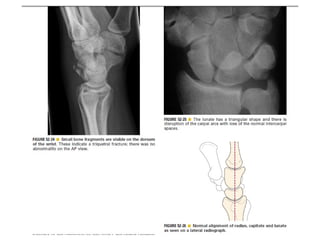

Skeletal trauma was presented by Dr Laith Fadhel with reference to Grainger's Diagnostic Radiology textbook. The presentation covered skeletal trauma as assessed through diagnostic radiology techniques. Key findings and treatments for skeletal injuries were likely discussed.